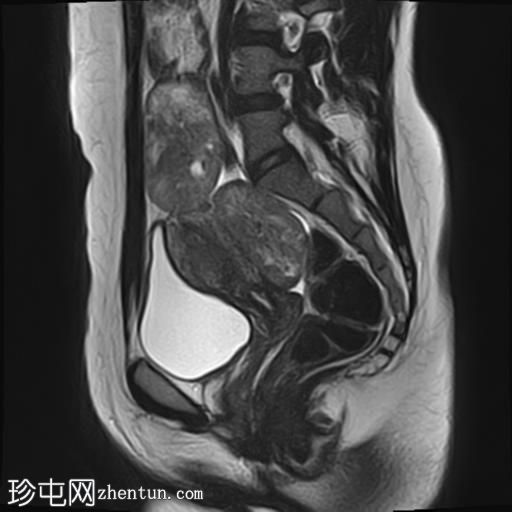

轴位T1加权像

增强脂肪抑制像

盆腔内可见多个边界清晰的肿块:

其中一个位于子宫上方,T2加权像呈中等信号,中心区域呈高信号,增强T1脂肪抑制像未见强化。右侧卵巢增大,增厚的血管蒂扭曲,未见强化,轴位和矢状位T2加权像均显示清晰。

另一个位于子宫后窝,T2加权像呈中等信号,增强扫描显示明显强化。

2个月前进行的MRI检查显示双侧卵巢肿块均有强化,右侧卵巢肿块未见扭转。